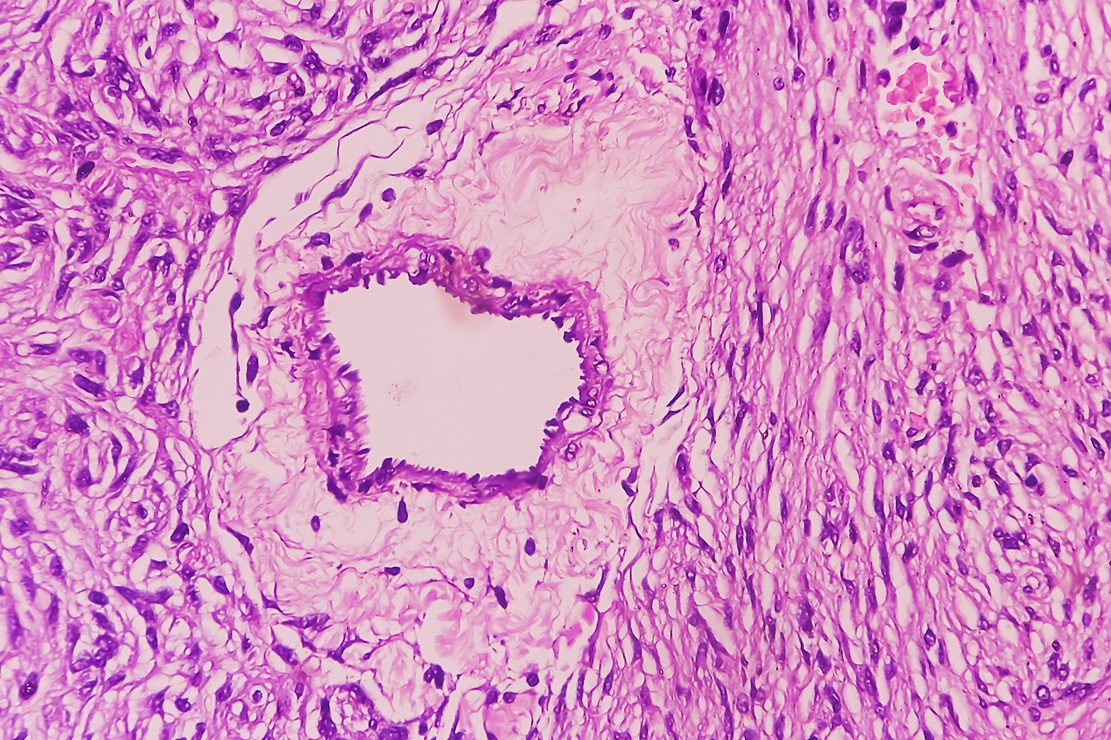

– Ta dziedzina jest niedochodowa. Procedury neuropatologiczne nie są refundowane przez NFZ, przez co jesteśmy kosztem dla szpitala. Naszą specjalizację trzeba wesprzeć, a nie likwidować – uważa prof. Wiesława Grajkowska. Neuropatolodzy zajmują się diagnostyką chorób ośrodkowego i obwodowego układu nerwowego, w tym nowotworów, chorób neurozwyrodnieniowych i demielinizacyjnych. W swojej pracy wykorzystują badania mikroskopowe, immunohistochemiczne i molekularne.

Kolejny obszar to diagnostyka nowotworów ośrodkowego układu nerwowego. – Rozpoznajemy je w oparciu o badania histopatologiczno-molekularne. W niektórych nowotworach markery molekularne określają stopień złośliwości, mają znaczenie prognostyczne i predykcyjne. Dzięki neuropatologii możliwe jest zastosowanie nowoczesnych terapii celowanych oraz kwalifikowanie pacjentów do leczenia zgodnie z aktualnymi standardami międzynarodowymi. Mimo problemów z refundacją są ośrodki w Polsce, które się tym zajmują – wyjaśnia prof. Wiesława Grajkowska.